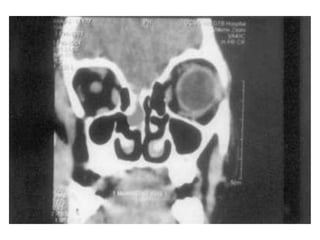

This document discusses sinus imaging using CT scans. It first describes the different sinus cavities in the anatomy: frontal, maxillary, nasal, ethmoid and sphenoid. Second, it lists common sinus pathologies seen on CT such as sinusitis, fungal sinusitis, deviated septum, sinus polyps, mucoceles, concha bullosa and sinus cancer. Finally, it presents two case studies and asks questions to test understanding of sinus conditions and anatomy.